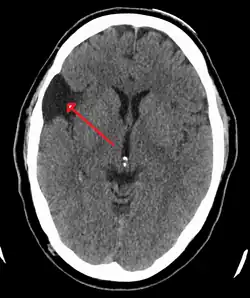

CT scan of a colloid cyst

The diagnostic process typically begins with a medical history workup followed by a medical examination by a physician. Imaging tests, such as CT scans and MRIs, help provide a clearer picture. The physician typically looks for fluid (or other bodily substance) filled sacs to appear in the scans, as is shown in the CT scan of a colloid cyst. A primary health care provider will refer an individual to a neurologist or neurosurgeon for further examination. Other diagnostic methods include radiological examinations and macroscopic examinations. After a diagnosis has been made, immunohistochemistry may be used to differentiate between epithelial cysts and arachnoid cysts.[2] These examinations are useful to get a general idea of possible treatment options, but can be unsatisfactory to diagnose CNS cysts.[3][5] Professionals still do not fully understand how cysts form; however, analyzing the walls of different cyst types, using electron microscopes and light microscopes, has proven to be the best diagnostic tool. This has led to more accurate cyst classification and correct course of action for treatments that are cyst specific. In the past, before imaging scans or tests were available, medical professionals could only diagnose cysts via exploratory surgery.[2]